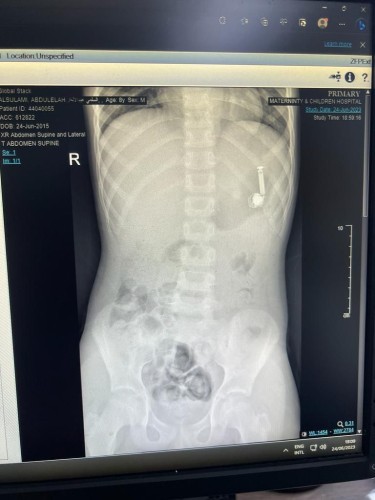

تمكن بفضل الله تعالى فريق طبي بمستشفى الولادة والأطفال عضو تجمع مكة المكرمة الصحي من إخراج سماعة جوال من داخل جوف طفل يبلغ من العمر ١٠ سنوات حيث حضر الطفل مع أهله إلى الطوارىء بعد ابتلاعه للسماعة.

في التفاصيل وصلت الحالة لقسم الطوارئ بالمستشفى حيث أخبر الأهل الطاقم الطبي أن ابنهم ابتلع السماعة وعلى الفور تم مناظرة الحالة وعمل الفحوصات الطبية اللازمة وشُكل فريق طبي من قسم المناظير وقسم التخدير للتعامل مع الحالة وتجهيز الطفل لعمل المنظار دون تدخل جراحي.

وتكللت العملية بالنجاح بفضل الله تعالى في وقت قياسي تم على إثرها ازالة السماعة والتأكد من صحة الطفل وقد غادر المستشفى وهو يتمتع بصحة جيدة – ولله الحمد.

الجدير بالذكر ان المستشفى استقبل أكثر من ٣٠٠ حالة ابتلاع لأجسام غريبة خلال العام الحالي، وقد تم التعامل بالمناظير مع ٣٥ حالة منها، وباقي الحالات اكتفت الفرق الطبية بمتابعتها حتى خروجها الآمن من الجسم .